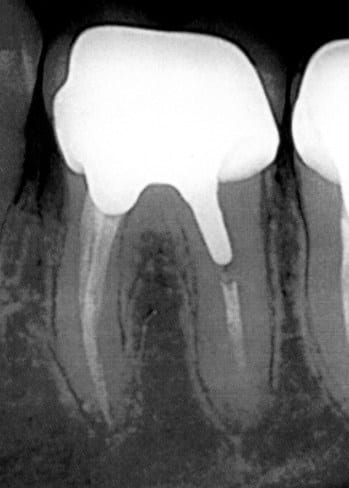

J'ai fait 2 endos dans la foulée sur un patient en janvier (36-37). Depuis le début il m'indique une sensibilité sur la 36. Effectivement, je teste à chaque visite, cette dent lui fait un peu mal à la percussion.

Je pensais au début à une arthrite persistante mais comme ça ne passe pas, j'ai pris une radio pour vérifier si tout va bien. Et là, à moins que ce soit un artefact, ça ressemble quand même bigrement à un granulome apical sur la distale...

On voit que l'obturation ne va pas jusqu'à l'apex mais je n'ai pas pu faire mieux, le canal doit sûrement partir en réseau.

Radio moche sur nonol, on y voit pas grand chose, sauf que ton endo est très courte en distal.

Si granulome il y a (le contraste n'est pas terrible) je ne vois pas l'interet de déposer pour tout refaire. Tu ne feras pas mieux.